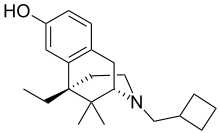

Others

- 1-Nitroaknadinine * 14-episinomenine

- 5,6-Dihydronorsalutaridine

- 6-Keto Nalbuphine

- Aknadinine

- Butorphanol

- Cephakicine

- Cephasamine

- Cyprodime

- Drotebanol

- Fenfangjine G

- Ketorfanol

- Nalbuphine

- Nalbuphone

- Tannagine

Structures

| Other Morphinans | ||||

|---|---|---|---|---|

1-Nitroaknadinine 1-Nitroaknadinine |

14-episinomenine 14-episinomenine |

5,6-Dihydronorsalutaridine 5,6-Dihydronorsalutaridine |

6-Keto Nalbuphine 6-Keto Nalbuphine |

Aknadinine Aknadinine |

Butorphanol Butorphanol |

Cephakicine Cephakicine |

Cephasamine Cephasamine |

Cyprodime Cyprodime |

Drotebanol Drotebanol |

Fenfangjine G Fenfangjine G |

Nalbuphine Nalbuphine |

Sinococuline Sinococuline |

Sinomenine Sinomenine |

Tannagine Tannagine |

Benzomorphans